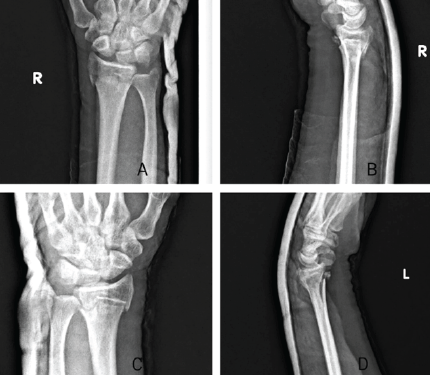

A 42-year-old right-handed male construction worker fell from a scaffold approximately 10 feet high. He landed with both arms outstretched and elbows extended. Upon presentation, the patient had gross deformity, pain, and swelling at both wrists and elbows. Upon inspection, deformities were seen on both wrists and elbows bilaterally. On examination, tenderness was found with a limited range of motion. Neurovascularity was intact in both upper limbs. X-rays revealed bilateral posterior elbow dislocation without associated fracture (Fig. 1a, b, c, d) and bilateral comminuted intra-articular distal radius fractures (AO 23-C2). (Fig. 2a, b, c, d). In the emergency setting, both elbow dislocations were promptly managed with closed reduction under sedation, and concentric reduction was confirmed on post-reduction radiographs (Fig. 3a, b, c, d). Both wrists were also reduced, and stabilization was done with slab application (Fig. 4a, b, c, d). Following initial stabilization and resolution of soft tissue swelling, the patient underwent staged open reduction and internal fixation of the bilateral distal radius fractures using a volar approach (modified Henry technique). Fixation was achieved using volar locking compression plates for both wrists (Fig. 5a, b, c, d).

Figure 4: `-reduction X-rays of right wrist in anteroposterior (a) and lateral (b) view and left wrist in anteroposterior (c) and lateral (d) view.